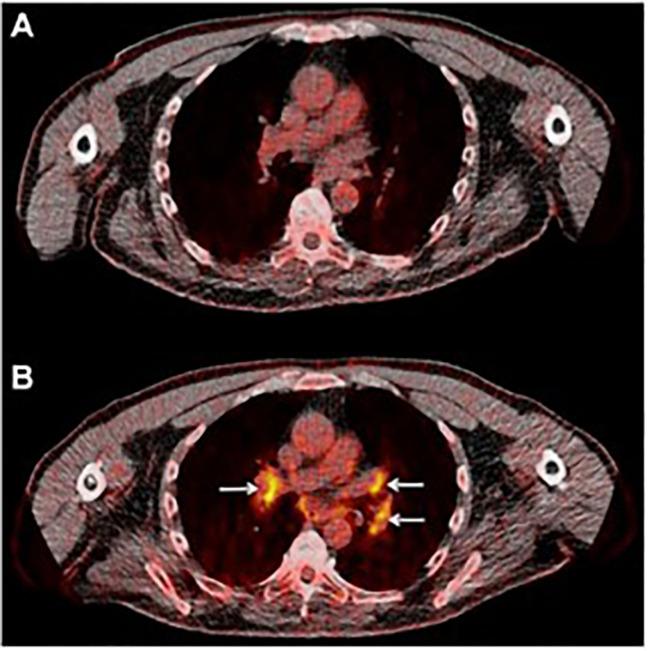

Unique patterns of response to immune checkpoint inhibitor therapy, discernable in the earliest clinical trials, demanded a reconsideration of the standard methods of radiological treatment assessment. Immunomonitoring, that characterizes immune responses, offers several significant advantages over the tumor-centric approach currently used in the clinical practice: 1) better understanding of the drugs' mechanism of action and treatment resistance, 2) earlier assessment of response to therapy, 3) patient/therapy selection, 4) evaluation of toxicity and 5) more accurate end-point in clinical trials. PET imaging in combination with the right agent offers non-invasive tracking of immune processes on a whole-body level and thus represents a method uniquely well-suited for immunomonitoring. Small molecule metabolic tracers, largely neglected in the immuno-PET discourse, offer a way to monitor immune responses by assessing cellular metabolism known to be intricately linked with immune cell function. In this review, we highlight the use of small molecule metabolic tracers in imaging immune responses, provide a view of their value in the clinic and discuss the importance of image analysis in the context of tracking a moving target.

独特的免疫检查点抑制剂治疗反应模式,在最早的临床试验中就已经显现,这要求重新考虑放射治疗评估的标准方法。免疫监测可以描述免疫反应,与目前临床实践中使用的以肿瘤为中心的方法相比具有几个显著优势:1)更好地了解药物的作用机制和治疗耐药性;2)更早地评估对治疗的反应;3)患者/治疗选择;4)评估毒性;5)临床试验中更准确的终点。PET 成像与合适的药物联合使用,可以在全身范围内非侵入性地跟踪免疫过程,因此是一种非常适合免疫监测的方法。小分子代谢示踪剂在免疫 PET 研究中被忽视,但它们可以通过评估与免疫细胞功能密切相关的细胞代谢来监测免疫反应,为我们提供了一种新的方法。在这篇综述中,我们强调了小分子代谢示踪剂在免疫反应成像中的应用,探讨了它们在临床中的价值,并讨论了在跟踪移动目标的背景下图像分析的重要性。